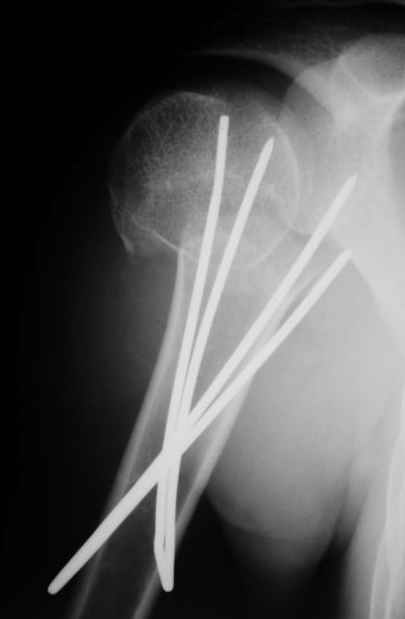

Уважаемые коллеги,

Посылаю послеоперационные Рг граммы.

Евгений И Чекашкин

Отправитель: Alexander Chelnokov 02 Декабрь 2004, 19:21

Поздравляю, получилось просто замечательно. Если можно, расскажи чуть подробнее, как делали - как вправляли, как вводили спицы, поворачивали ли их?

Отправитель: Evgueny Tschekashkin 02 Декабрь 2004, 19:22

Спасибо за поздравления:-))

Я и сам доволен результатом. В предпоследнем письме я кратко описал ход операции - закрыто репонировать не удалось( 2 недели с момента травмы и 1 неделя после неудачной репозиции) после удаления пучков спиц, пришлось сделать - 2см разрез на уровне перелома и с помощью периостального элеватора (золотое правило механики) *одеть* головку на дистальный отломок.

Спицы проводил через старые отверстия, вращая пучок импактором- направителем при его введении в головку.